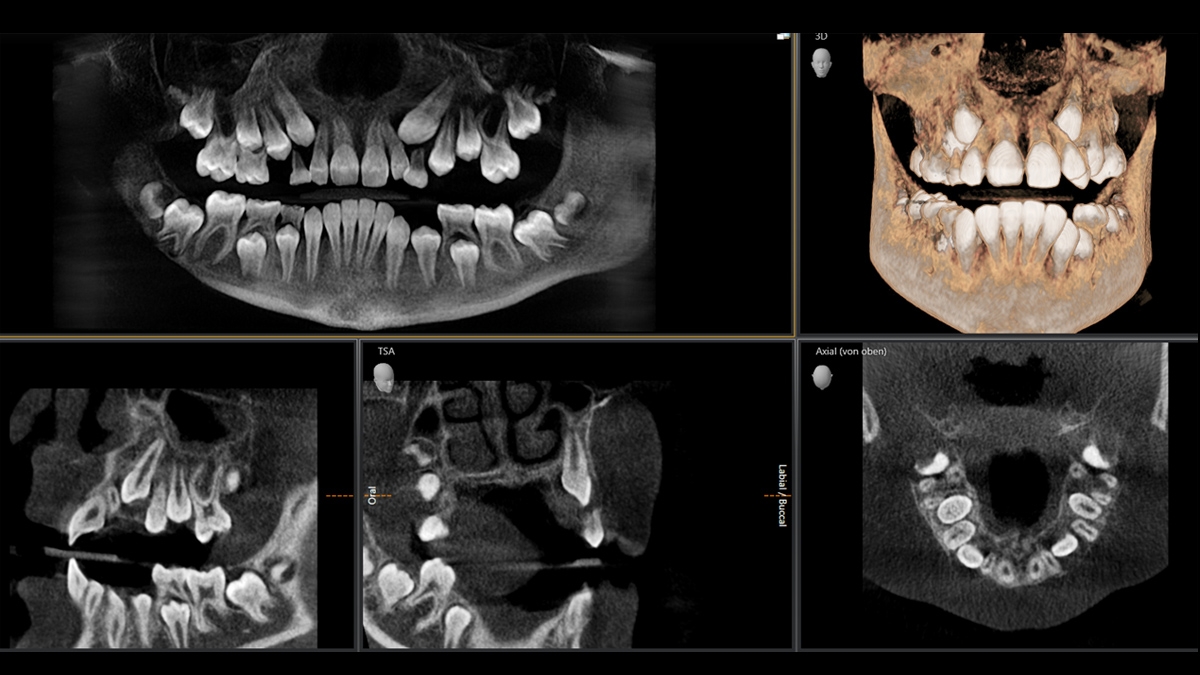

Mientra trabaja con niños, es esencial tener un nivel adicional de cuidado, sin embargo, existirán casos en los que las imágenes 2D no pueden proporcionar la información necesaria. Con el modo de dosis baja ahora ambos mundos pueden combinarse: el nivel de dosis baja de una imagen panorámica para proteger a los pacientes jóvenes y el nivel de información de una imagen CBCT para el mejor tratamiento.